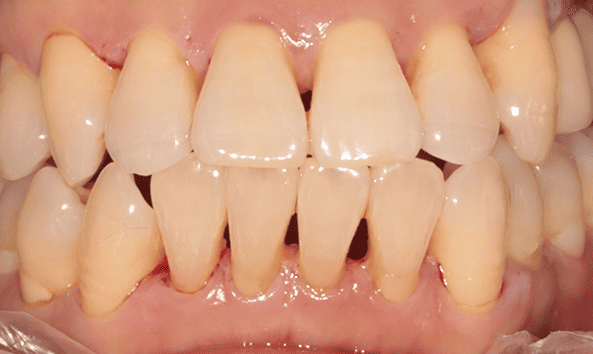

붓고 피나는 잇몸을 건강하게 잇몸치료로 회복하세요!

건강한 치아는 건강한 잇몸이 있기에 존재합니다. 성인의 절반 이상이 잇몸 질환을 모르고 방치하고 있습니다. 잇몸질환, 꾸준한 관리를 통해 개선해드리겠습니다.

잇몸 질환 치료에는 비수술적 치료와 수술적 치료 방법이 있습니다.

건강한 잇몸

치주낭 길이 3mm 이하

스케일링 치료

치은염

치주낭 길이 3~5mm 이하

치근활택술 치료

초기 치주염

치주낭 길이 5~7mm 이하

치주소파술 치료

중기 치주염

치주낭 길이 7mm 이상

치주 수술